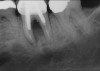

Fig 15. (Case 3) Radiograph of tooth No. 19, which had a hopeless prognosis.

Figure 15

Fig 16. Radiograph of extraction socket. Buccal and lingual plates were defective.

Figure 16

Fig 17. Bone graft was placed in the socket and a d-PTFE barrier was used to cover the graft. The bone graft material was placed beyond the alveolar housing to accommodate shrinkage of graft material and to facilitate attaining a wide alveolar ridge. The barrier was removed after 6 weeks.

Figure 17

Fig 18. Healed ridge exposed after 6 months.

Figure 18

Fig 19. Implant inserted into healed ridge.

Figure 19